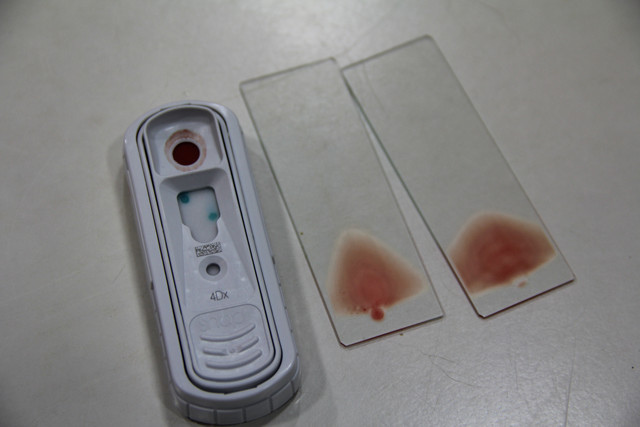

麻醉時間只有三十分鐘,要趕緊把握時間,做抽血、血液檢查與4D檢查。

4D檢查出來,小黑患有心絲蟲,

目前就先給小黑吃兩個月的四環素,然後再打心絲蟲針。